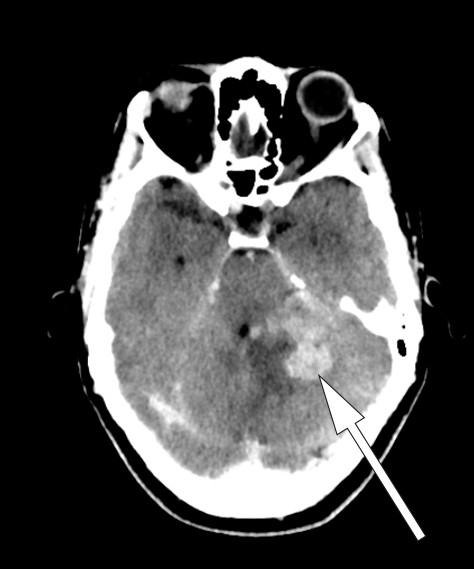

Dag 6 ble hodepinen verre, i tillegg så man parese av n. abducens. Pasienten var vedvarende febril, temperaturen lå mellom 38,0 °C og 38,5 °C. Ny CT caput med kontrast viste kontrastoppladning ved tentoriet, i cerebellum, i pons samt i høyre oksipitallapp med omkringliggende ødem (fig 2). MR cerebrum uten kontrast viste lavt signal på T2-vektet sekvens, tilsvarende de kontrastladende lesjonene (fig 3).